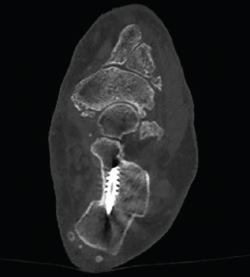

Los procedimientos que acompañan a la OCP en la corrección de las deformidades suelen marcar el tiempo de descarga e inmovilización. Cuando la osteotomía es el único procedimiento óseo de la corrección, se autoriza una carga protegida con bota de tipo Walker e inicio de ejercicios de flexoextensión de tobillo a las 4-5 semanas, para posteriormente iniciar progresivamente la carga completa 2 semanas después (Figuras 10 y 11).

Figura 11. Detalle de la osteotomía en la tomografía computarizada a los 3 meses.